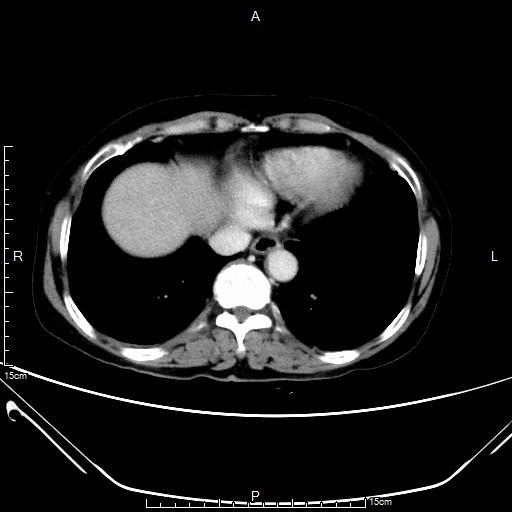

老年女性,胃腺癌并肝多发转移,行6周期姑息化疗,病情得到控制良好(部分缓解)。

CT显示肝左、右叶多发转移瘤

- CT显示肝左、右叶多发转移瘤较前明显缩小

CT显示肝左、右叶多发转移瘤较前明显缩小